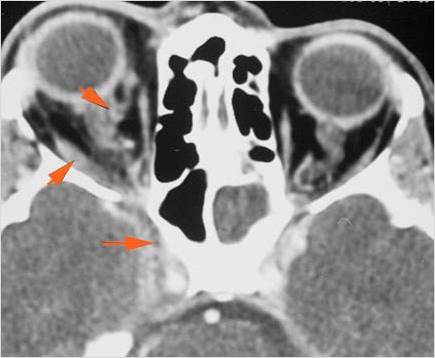

The extraconal orbital fat is abnormal.

There is a subperiosteal abscess or edema along the medial wall, roof or floor of the orbit.

The extraocular muscles are swollen or otherwise abnormal.

There is bone erosion along the walls of the orbit.